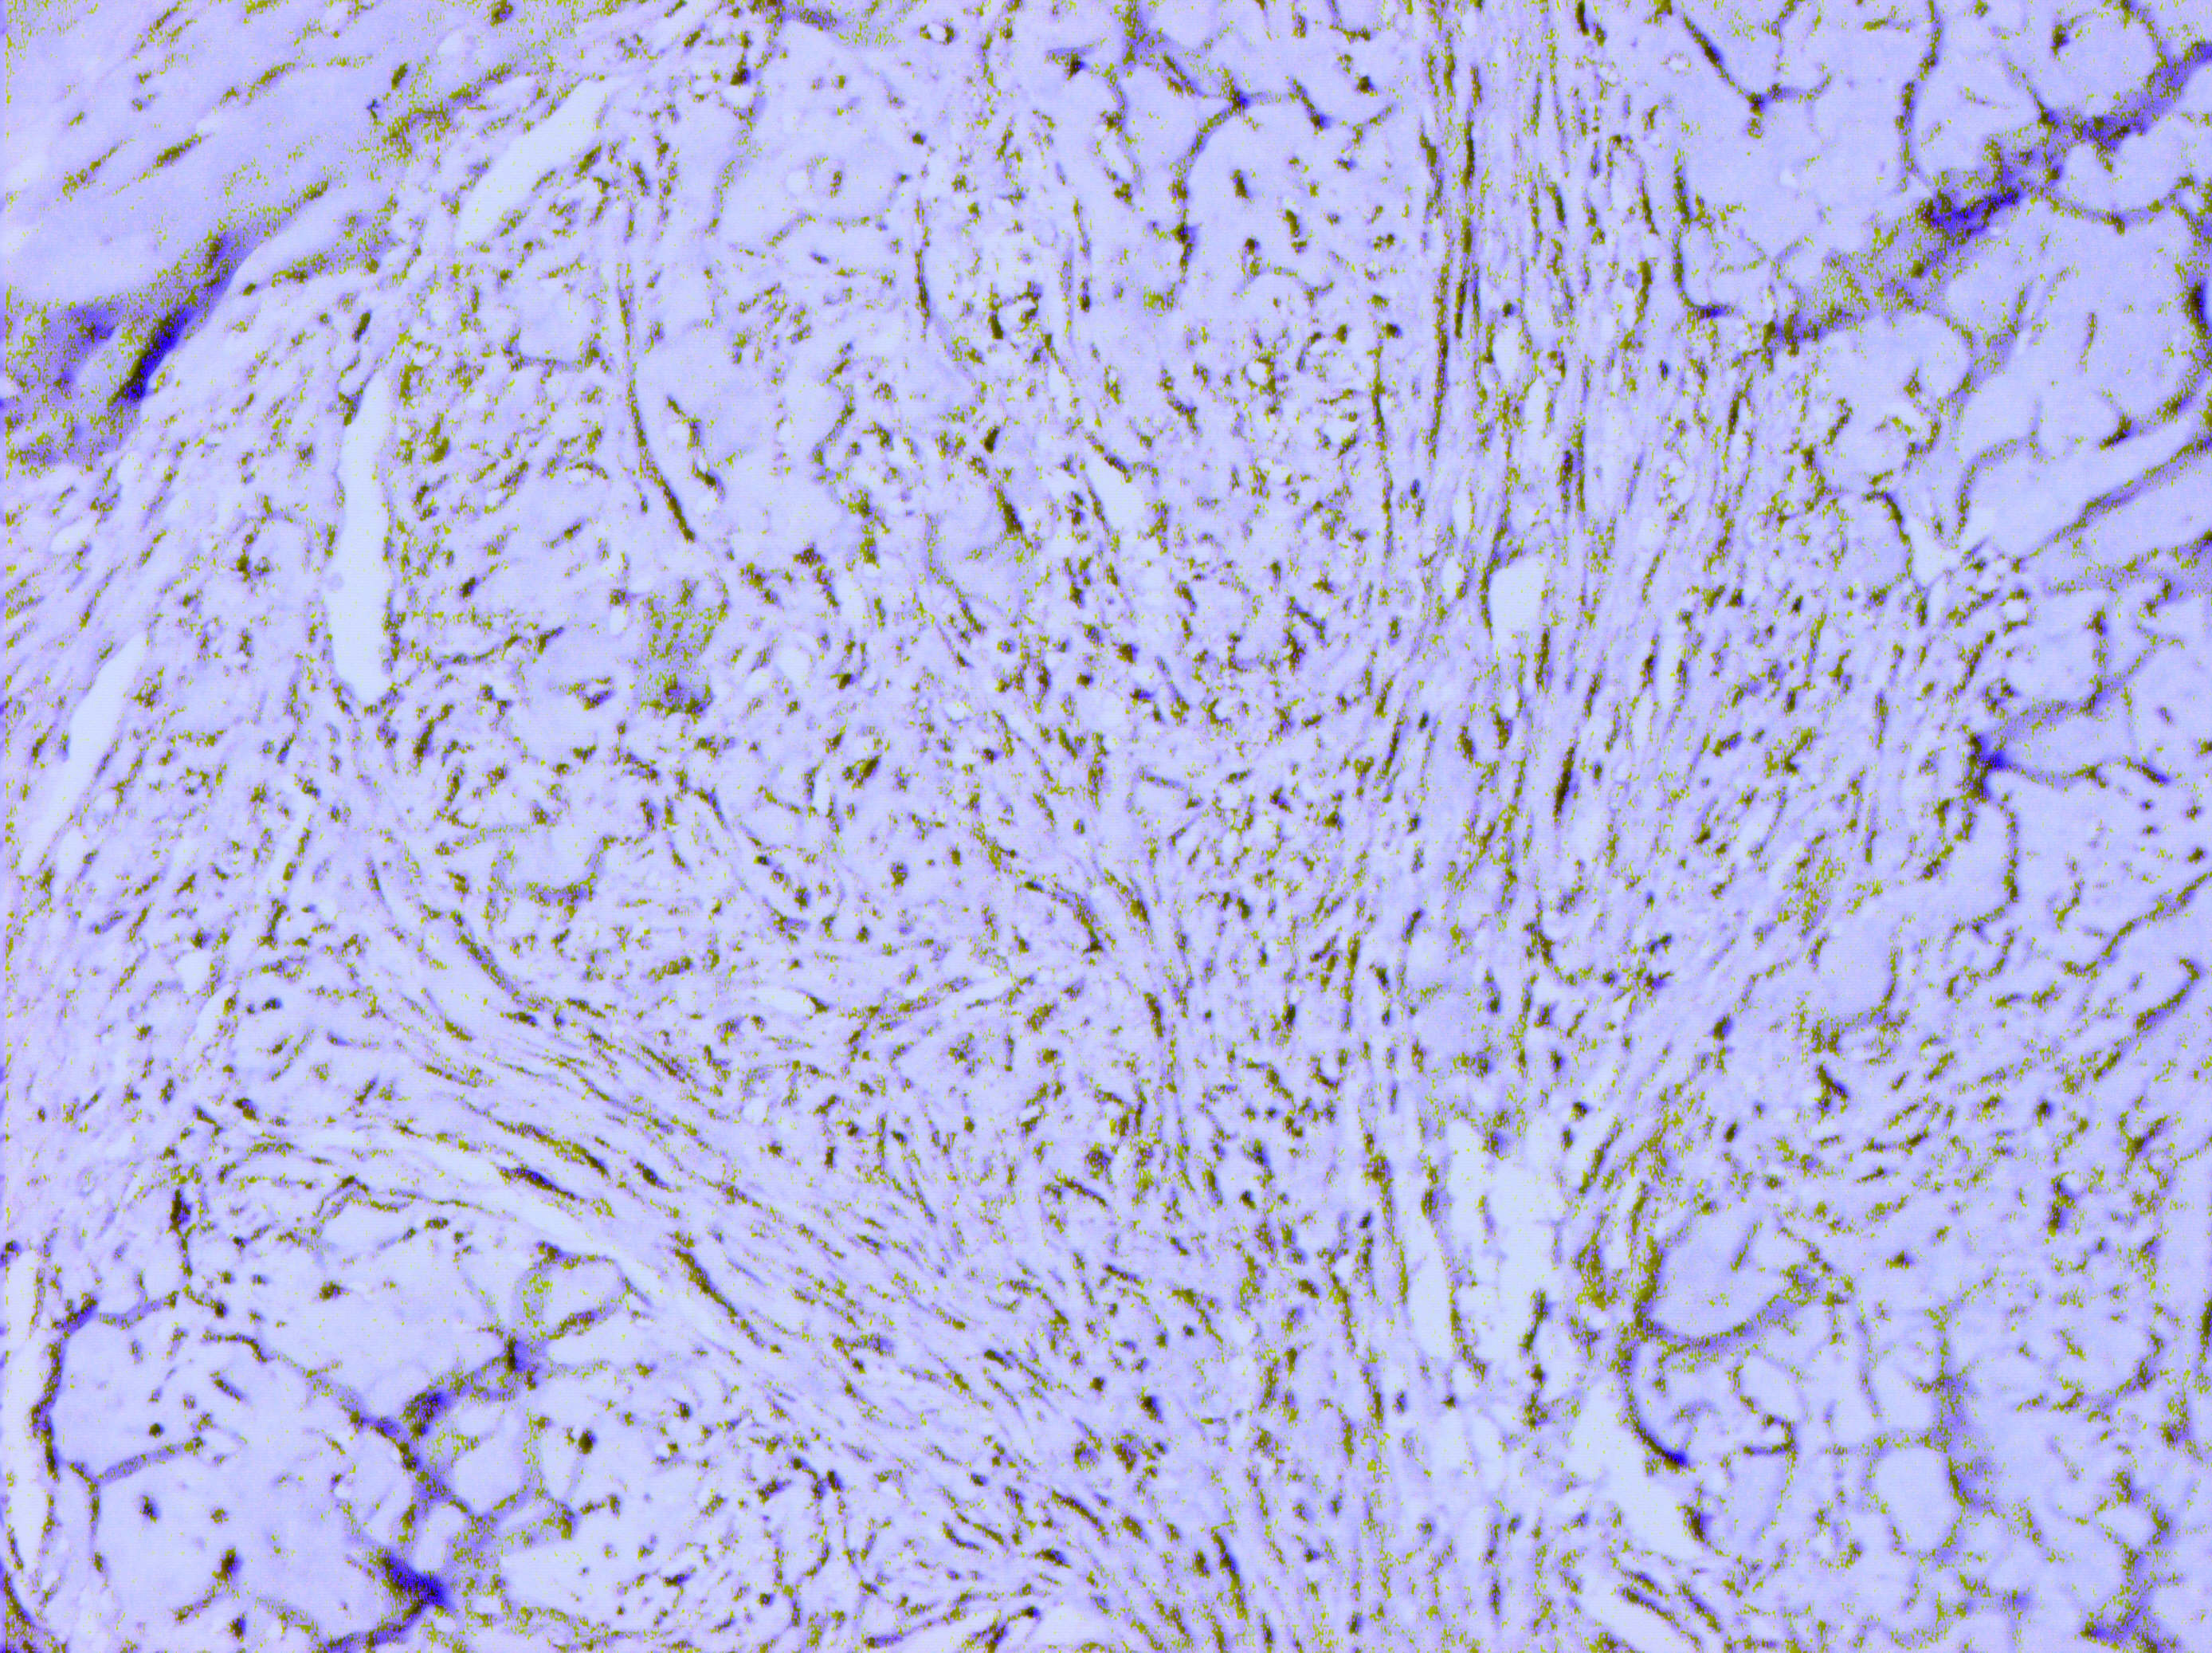

Матеріали та методи. Для ІГХ-дослідження було відібрано 60 парафінових блоків пухлин, у яких гістологічно було верифіковано діагноз саркоми (42) та філоїдної пухлини (18). ІГХ-дослідження проводили з використанням спектра відповідних антитіл, який включав маркери панцитокератинів (клон AE1/AE3); ERG (клон EP111); SOX-10 (клон EP268); TLE1 (клон 1F5); кальдесмону (клон h-CD); міогеніну (Myf-4) (клон F5D); MyoD1 (клон EP212); десміну (клон D33); MDM2 (клон 1B10); CDK4 (клон EP180); CD68 (клон PG-M1); CD34 (клон QBEnd 10); CD31 (клон JC70A); бета-катеніну (клон betaCatenin-1); гладеньком’язового актину альфа (клон 1A4); актину (клон HHF35); епітеліального мембранного антигену (EMA, MUC1) (клон E29). Також визначали рівень експресії маркера проліферації Ki-67 (клон MIB-1). Дослідження проводили в лабораторії CSD Health Care, м. Київ.

Результати дослідження та їх обговорення. Після проведених імуногістохімічних досліджень виявилось, що із 12 сарком без уточненого гістотипу в 9 випадках були плеоморфні саркоми, у 2-х – міофібробластні саркоми, та одна остеосаркома. Із 27 блоків ангіосарком імуногістохімічно було підтверджено 17 (63,0 %), інші 10 (37,0 %) виявились карциномами. Фібросаркоми (три гістологічні блоки) були повністю підтверджені імуногістохімічно. Серед 18 гістологічних блоків філоїдних пухлин проміжного типу у двох випадках (11,1 %) було встановлено злоякісний варіант ФП.